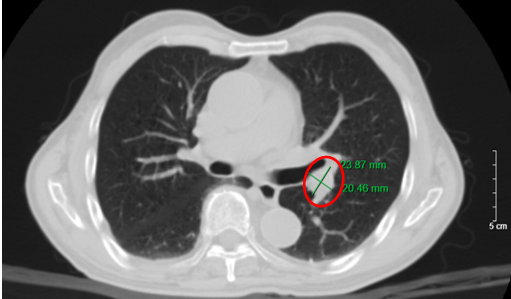

Hình 1. Hình ảnh nhu mô thùy trên phổi có nốt bờ không đều, tua gai, đường kính 26×17 mm (vòng tròn đỏ) trên phim chụp cắt lớp vi tính (cửa sổ trung thất).

Hình 2. Hình ảnh khối u bờ tua gai, đường kính 26×17 mm (vòng tròn đỏ), kèm hình ảnh dày tổ chức kẽ kèm các dải xẹp phổi nhu mô phổi trái. Giãn phế nang trung tâm lan tỏa rải rác nhu mô phổi, trên phim chụp cắt lớp vi tính (cửa sổ nhu mô).